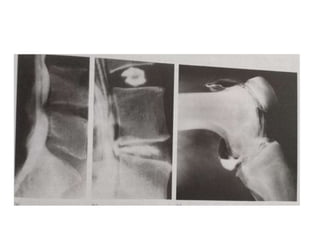

COMPUTED TOMOGRAPHY ( CT )

• CT SCAN produces sectional images through selected tissue

• As compared to conventional tomography , computed tomography

produces trans – axial images ( transverse anatomical sections )

• In new multislice CT scanners , 3D surface rendered

reconstructions & volume rendered reconstructions - help in

demonstrating anatomical contours

CLINICAL APPLICATIONS OF CT SCAN

• Since it provides excellent contrast resolution and spatial localization

it’s ideal for evaluating

Acute trauma to the head , spine , chest , abdomen & pelvis

• Better than MRI - fine bone detail & soft tissue calcification

• Invaluable tool in pre operative planning in secondary fracture

management

• Routinely used for vertebrae , acetabulum , tibial plataeu , ankle & foot

injuries - complex ( intraarticular fractures ) & fracture dislocations

COMPUTED TOMOGRAPHY (CT ) • CT SCAN produces sectional images through selected tissue planes - but with greater resolution • As compared to conventional tomography , computed tomography produces trans – axial images ( transverse anatomical sections ) • In new multislice CT scanners , 3D surface rendered reconstructions & volume rendered reconstructions - help in demonstrating anatomical contours

CLINICAL APPLICATIONS OFCT SCAN • Since it provides excellent contrast resolution and spatial localization it’s ideal for evaluating Acute trauma to the head , spine , chest , abdomen & pelvis • Better than MRI - fine bone detail & soft tissue calcification • Invaluable tool in pre operative planning in secondary fracture management • Routinely used for vertebrae , acetabulum , tibial plataeu , ankle & foot injuries - complex ( intraarticular fractures ) & fracture dislocations • Assessment of bone tumours ( size & spread ) • Can be employed for guiding soft tissues & bone biopsy